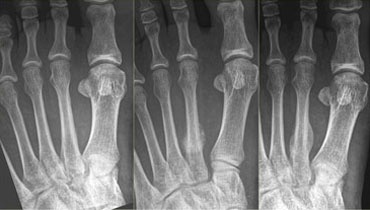

Typical stress fracture of the distal shaft of the second metatarsal not seen on initial radiograph (left). Callus formation is seen at 4 weeks follow up. Typical stress fracture of the distal shaft of the second metatarsal not seen on initial radiograph (left). Callus formation is seen at 4 weeks follow up.

On the left a 42-year old female who walks long distances and has been experiencing forefoot pain for a month.

On the initial radiograph no fracture is seen.

After 4 weeks, a follow up radiograph clearly marks callus formation at the site of the stress fracture.